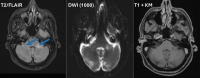

Abbildung 2: Patientin A: cMRT vom September 2023 (T2-Sequenz, T1-Sequenz mit KM): neue T2-hyperintense und T1-hypointense Läsion links cerebellär (blaue Pfeile) ohne Kontrastmittelaufnahme; DWI-Sequenzen wurden nicht durchgeführt